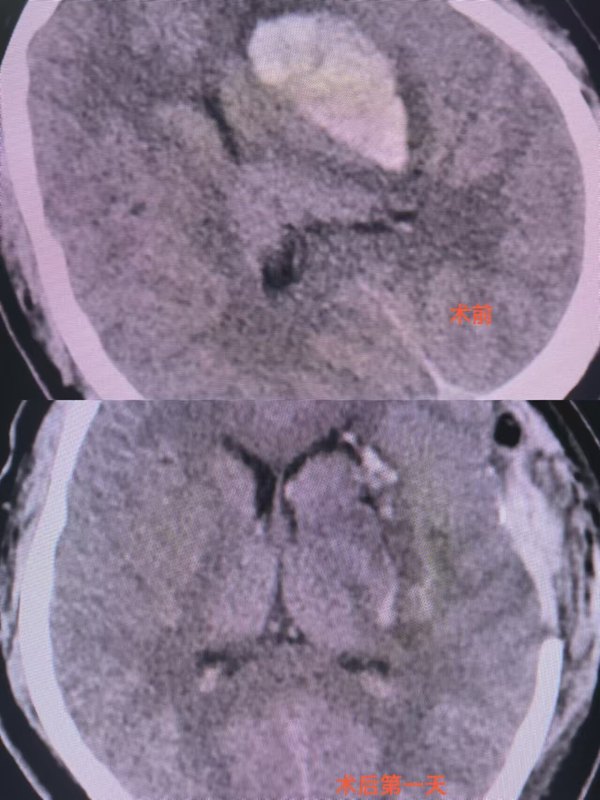

腦血腫康復(fù)案

上半年神經(jīng)外科(腦外科)團(tuán)隊(duì)和手術(shù)室、麻醉科、重癥醫(yī)學(xué)科、康復(fù)科、急診科、檢驗(yàn)科及影像科等科室通力合作,成功的搶救一危急患者,挽救了一個(gè)家庭,患者重新完美的投入工作?;颊撸?6歲男性,有高血壓病史,2024年3月5日突發(fā)昏迷,右側(cè)肢體全癱,肌力0級,急診行去骨瓣減壓術(shù)+腦內(nèi)血腫清除術(shù)。2024年3月18日患者恢復(fù)意識(shí),并行康復(fù)治療。并于2024年4月23日步行來院行顱骨修補(bǔ)術(shù),患者出院時(shí)四肢活動(dòng)正常,肌力Ⅴ級,正常上班投入工作中。這也是我院多科室協(xié)力合作成功的又一典范。